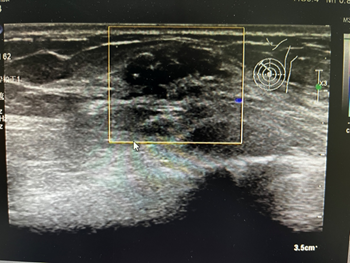

形态较规整,但内部还是不均匀,BI-RADS  4a类

BI-RADS  5:高度可能恶性,超声声像图恶性特征明显的病灶归于此类,其恶性可能性≥95%,应开始进行积极的治疗,经皮穿刺活检或手术治疗。

形态不规则,边界部分成角,条状血流信号,BI-RADS  5类